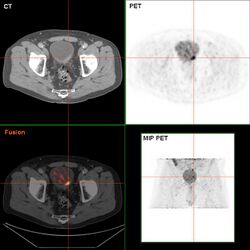

Bladder wall thickening due to cancer

Bladder tumor in FDG PET due to the high physiological FDG-concentration in the bladder, furosemide was supplied together with 200 MBq FDG. The uptake cranial to the lesion is a physiological uptake in the colon.

If invasive or high grade (includes carcinoma in situ) cancer is detected on TURBT, an MRI and/or CT scan of the abdomen and pelvis or urogram and CT chest should be conducted for disease staging and to look for cancer spread (metastasis).[56] Increase in alkaline phosphatase levels without evidence of liver disease should be evaluated for bone metastasis by a bone scan.[57] Although 18F-fluorodeoxyglucose (FDG)-positron emission tomography (PET)/CT has been explored as a viable method for staging, there is no consensus to support its role in routine clinical evaluations.[54]